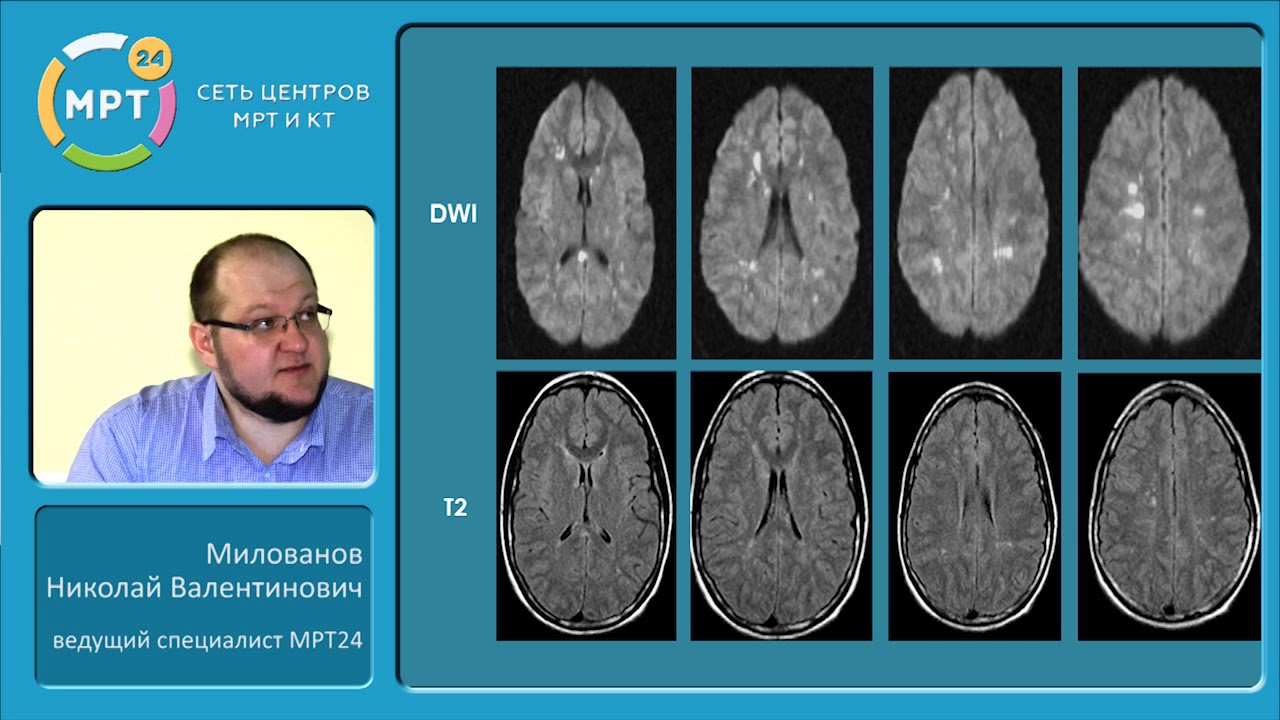

Что покажут снимки МРТ головы при аксональном повреждении головного мозга

- Картина на Т2*-ВИ обусловлена влиянием гемосидерина, вследствие геморрагических «травм от сдвига»

- ИКД снижен

- Обычно на границе серого и белого вещества

- Линейная или овальная форма

- Отсутствие перифокального отека

- Часто обнаруживается только при гистологическом исследовании, так как многие повреждения, особенно негеморрагические, при МРТ не определяются.